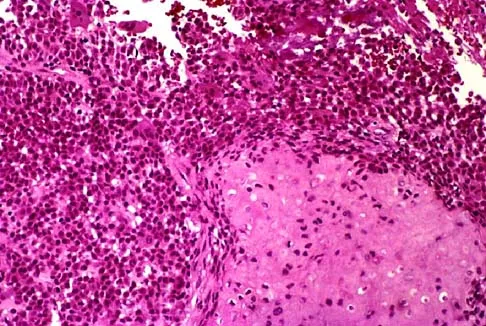

A 30-year-old woman has pain in her right hand. The radiograph, CT scan, and biopsy specimen are seen in Figures 38a through 38c. What is the most likely diagnosis?

Explanation